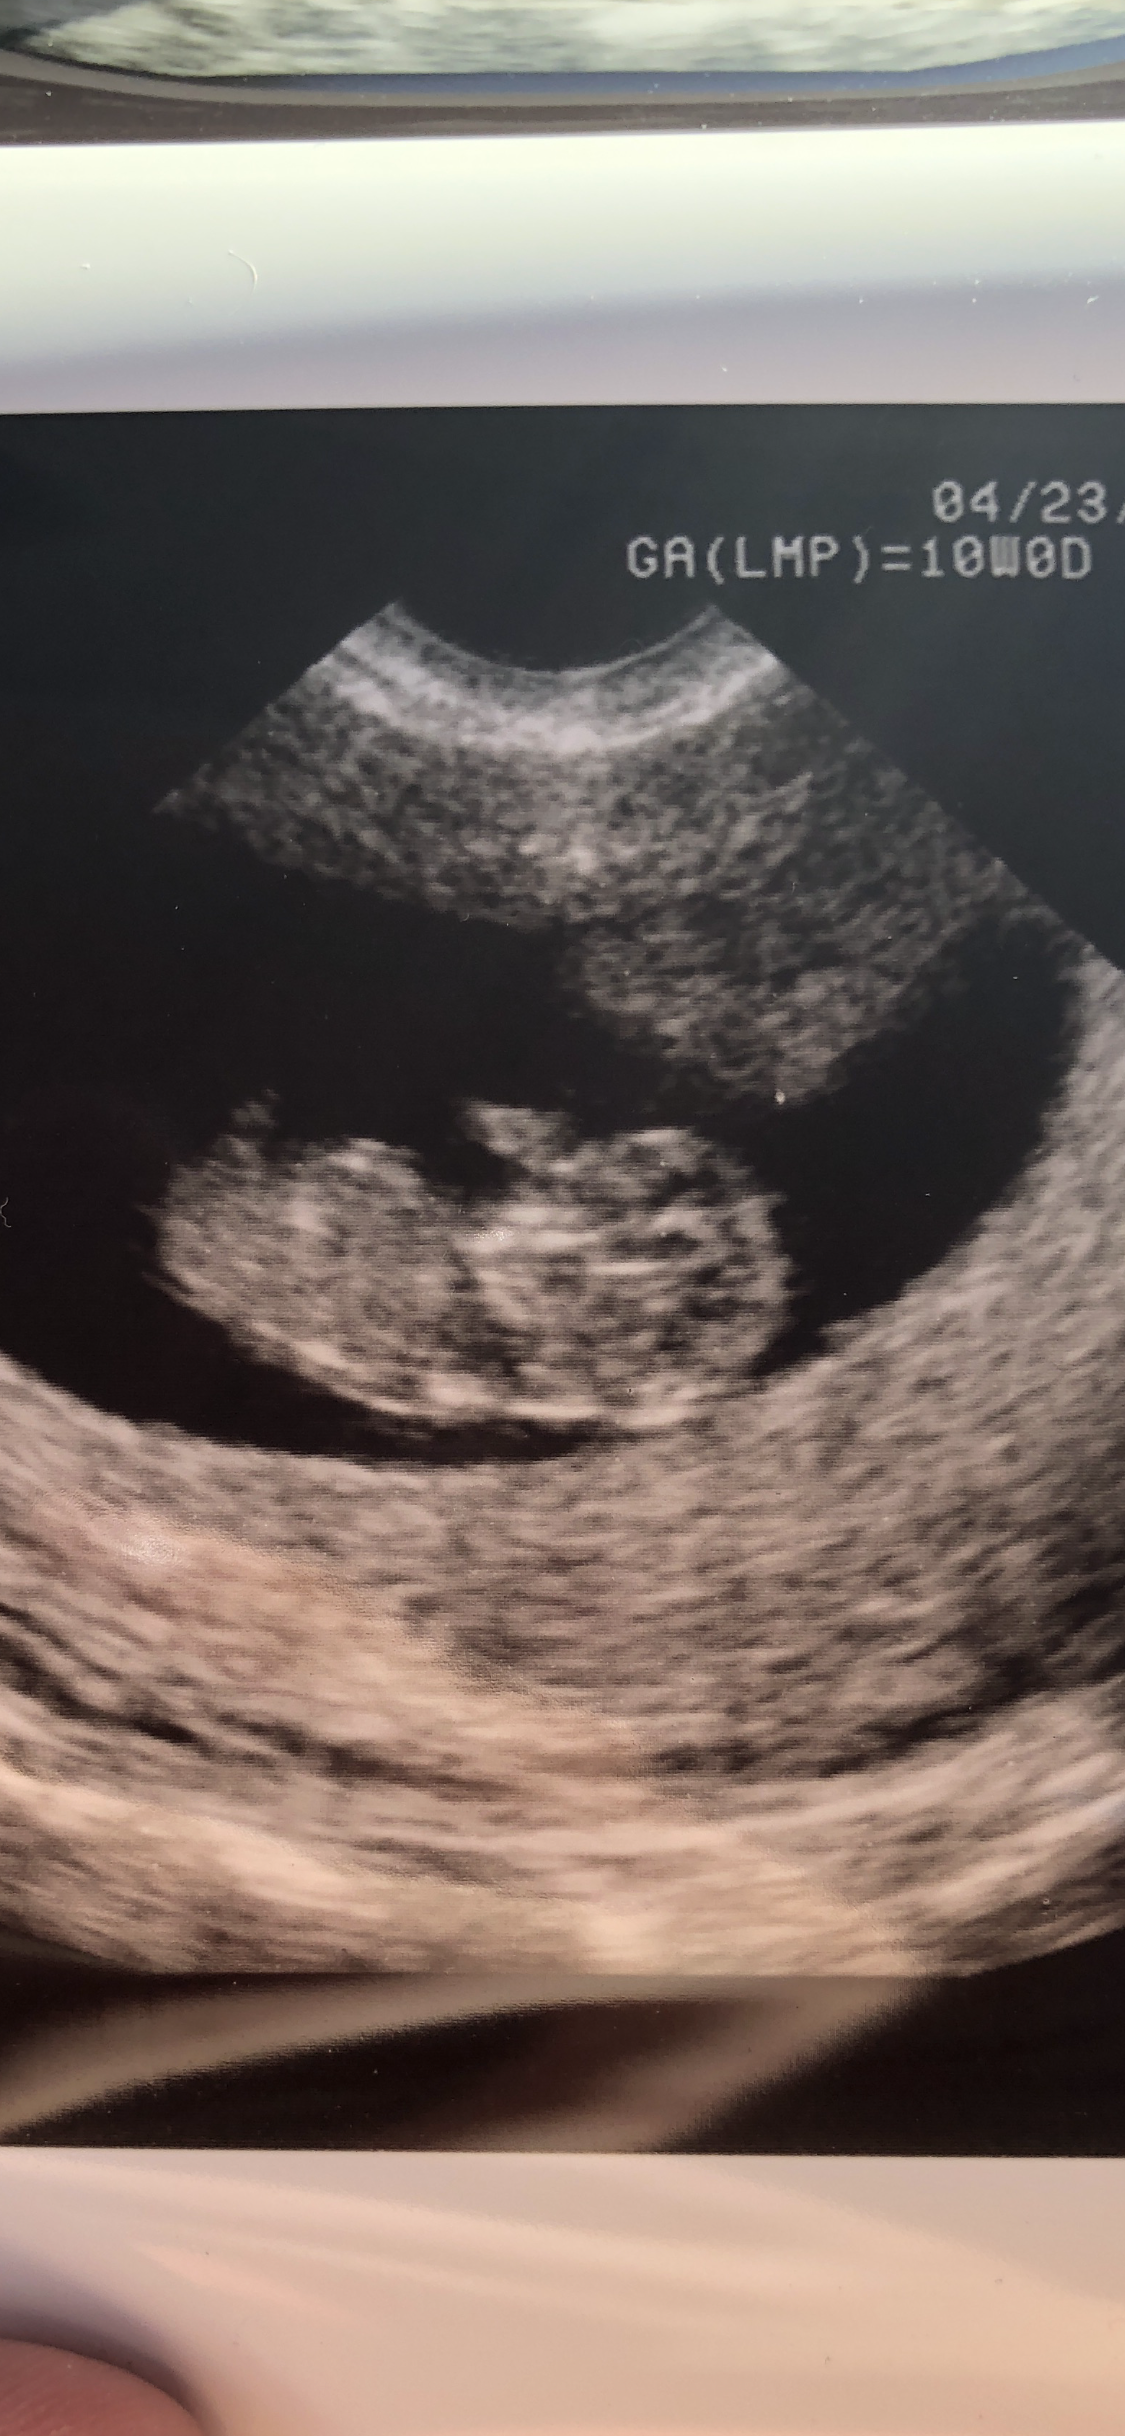

Our little one was 10w 2d at the US, I am now 11w 1d! We have a wiggle worm! He/she was all over the place! HR 170. Love this baby so much already and feeling so blessed! Due 11/27!